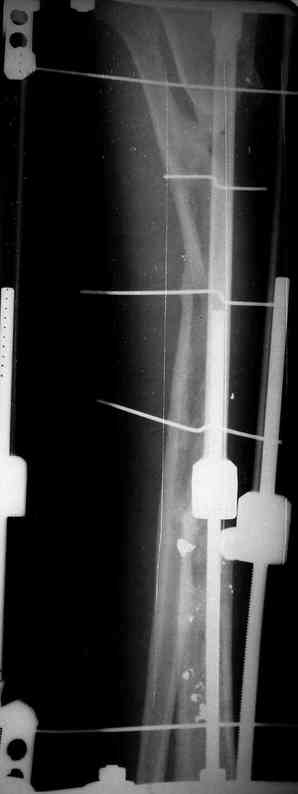

3,4 - через 4 недели наложен спице-стержневой аппарат, произведена остеотомия большеберцовой кости в верхней трети, раны зажили, проводилась дистракция в аппарате.